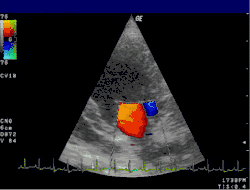

- Der Farbdoppler hilft, Klappeninsuffizienzen und -stenosen zu lokalisieren und zu quantifizieren. In einer anderen Geräteeinstellung wird der Farbdoppler für Gewebe optimiert und stellt die Bewegung der Herzwand dar. Anwendungen des Gewebedopplers sind Gegenstand der Forschung.